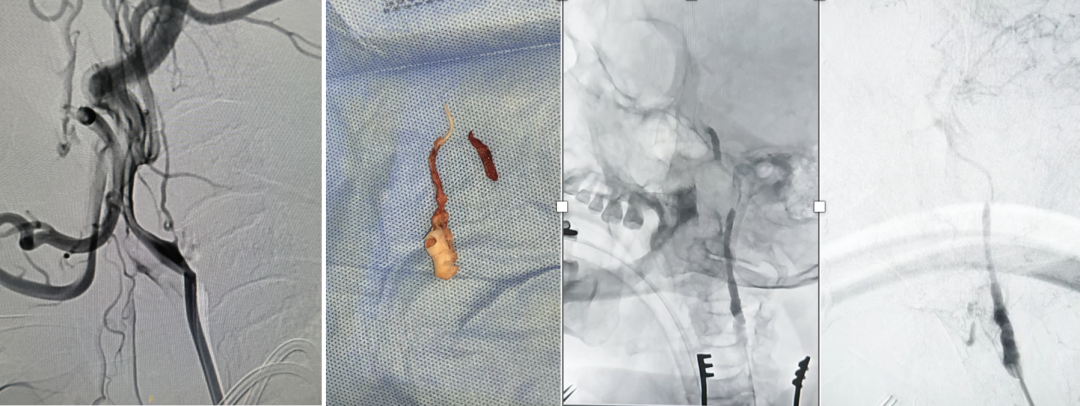

典型病例与教训

病例1(男性,76岁)

Wingspan支架植入后血流改善,但近端夹层需追加Precise支架

病例2(男性,79岁)

复合手术后并发海绵窦瘘,需弹簧圈+覆膜支架补救